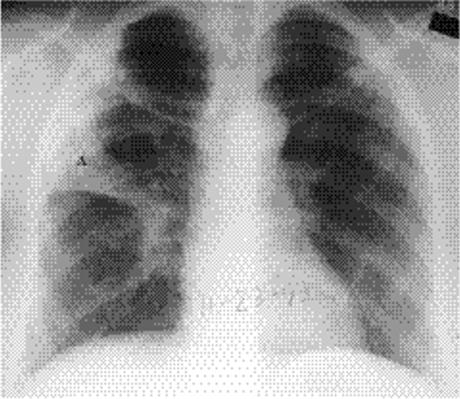

Focal opacity may be visible, especially when comparing one lung with the other on the frontal projection. On the lateral projection attention should be directed over the thoracic spine, the cardiac silhouette, and the retrosternal and retrocardiac regions, where faint opacity may otherwise escape detection (Figs. 5.1 and 5.2).

Figure 5.1 Opacity in pneumonia. (A) Posteroanterior and (B) lateral chest radiographs: minimal right basilar opacity, much better seen on the lateral view overlying the heart (P).